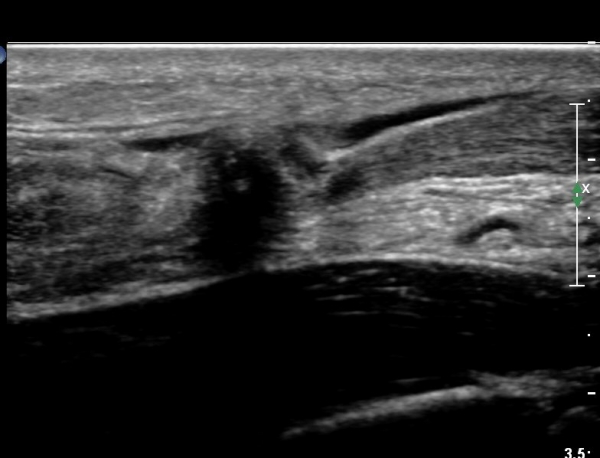

¾ÆÅ³·¹½º°Ç Á¾´Ü¸é°Ë»ç¿¡¼ ¾ÆÅ³·¹½º°Ç Àú¿¡ÄÚ ºÎÁ¾, ¿¬°á¼º ¼Ò½Ç, °ÇÁÖÀ§ ¼ö¾×Àú·ù ¼Ò°ßÀ» º¸ÀÓ(»çÁø 2, 3, 4, 5).